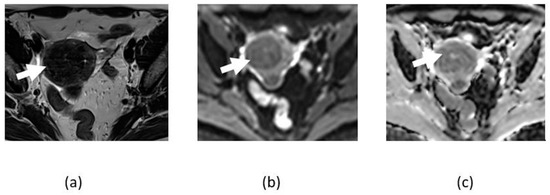

3.2. Adnexal Torsion

- Agostinho, L.; Horta, M.; Salvador, J.C.; Cunha, T.M. Benign ovarian lesions with restricted diffusion. Radiol. Bras. 2019, 52, 106–111. [Google Scholar] [CrossRef]

- Lall, C.; Bura, V.; Lee, T.K.; Bhosale, P.; Faria, S.C.; Choi, J.I.; Wang, Z.J. Diffusion-weighted imaging in hemorrhagic abdominal and pelvic lesions: Restricted diffusion can mimic malignancy. Abdom. Radiol. 2018, 43, 1772–1784. [Google Scholar] [CrossRef]

- Balaban, M.; Idilman, I.S.; Toprak, H.; Unal, O.; Ipek, A.; Kocakoc, E. The utility of diffusion-weighted magnetic resonance imaging in differentiation of endometriomas from hemorrhagic ovarian cysts. Clin. Imaging 2015, 39, 830–833. [Google Scholar] [CrossRef]

- Lee, N.K.; Kim, S.; Kim, K.H.; Suh, D.S.; Kim, T.U.; Han, G.J.; Lee, J.W.; Kim, J.Y. Diffusion-weighted magnetic resonance imaging in the differentiation of endometriomas from hemorrhagic cysts in the ovary. Acta Radiol. 2016, 57, 998–1005. [Google Scholar] [CrossRef]